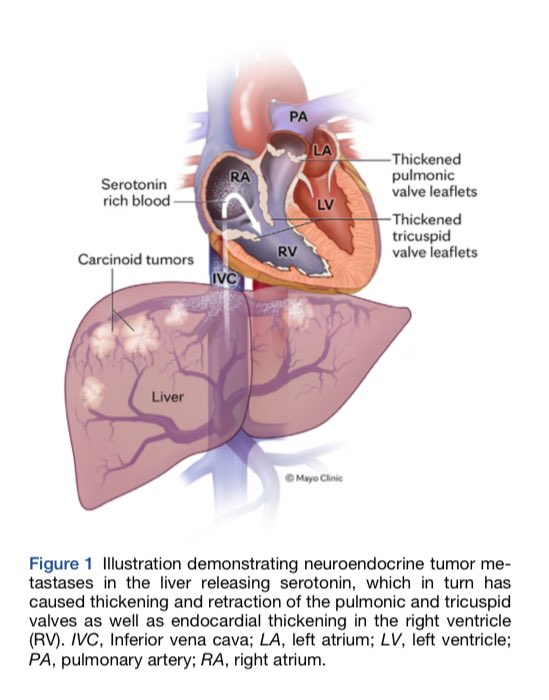

🔵 Echocardiographic Evaluation of Carcinoid Heart Disease @JournalASEcho #Cardiology #CardioEd #echofirst #FOAMed